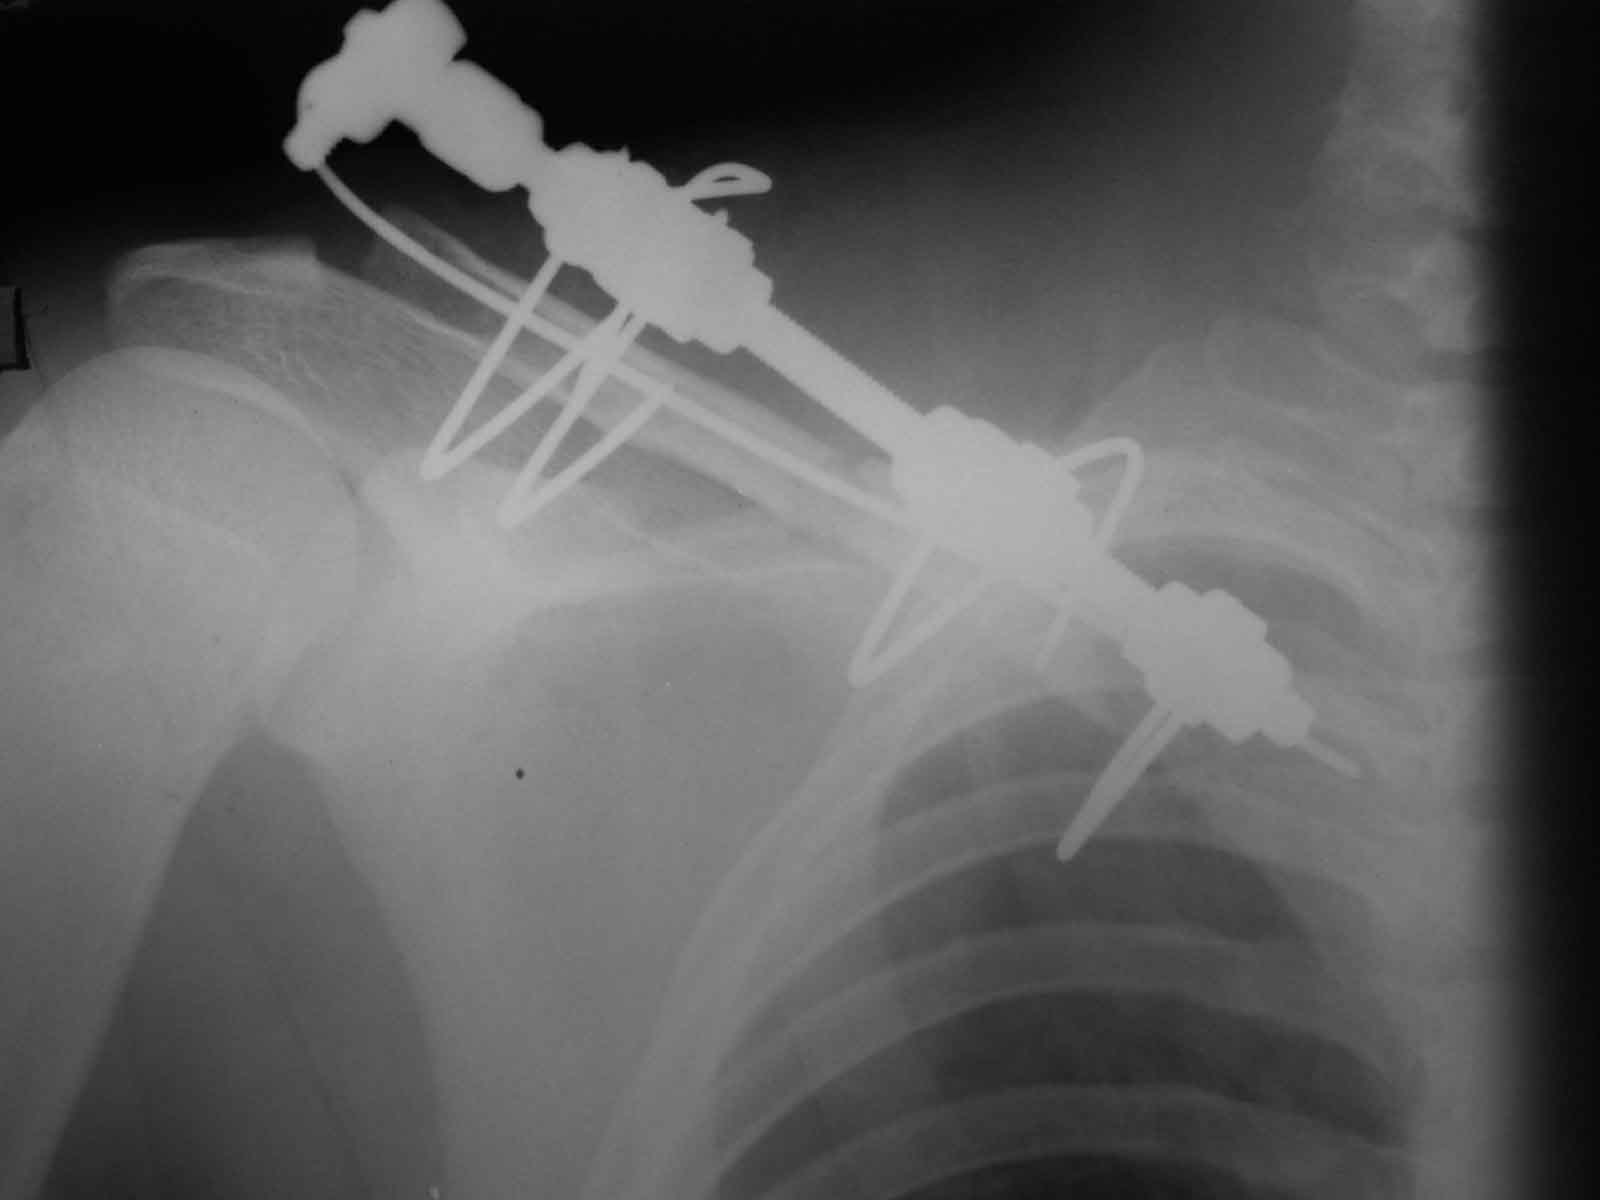

Один из вариантов, что удалось быстро найти, позже еще найду, но схема примерно такая (первое

вложение).

Мужик кочегар, срок нетрудоспособности 7 недель. Наружную конструкцию сняли через 3 недели. Далее без иммобилизации. Погруженную спицу можно убрать и через несколько месяцев, если жить не мешает.

Раньше не погружали, на рентгенограммах и натуре видно (последние 2 вложения). Как вариант спицы в периферическом отломке могут крепится на трехдырочную приставку, что дает возможность компрессии.